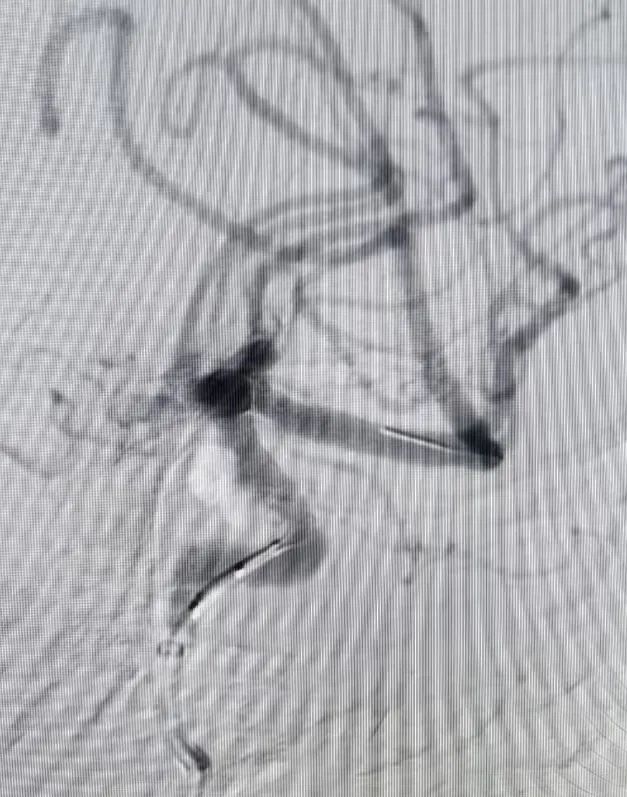

硬脑膜动静脉瘘患者同样在个性化方案中重获新生。患者因反复头晕,在外院怀疑静脉畸形,来到东方总院后,脑血管造影明确为硬脑膜动静脉瘘。通过详细的沟通,家属选择介入栓塞,吴全主任团队采用介入打胶栓塞的治疗方式,精准地堵住异常血管,一次性完全栓塞,术后患者头晕症状消失,生活质量大幅提升。